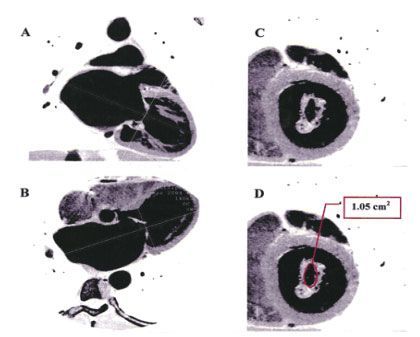

![]() |

| Рис.35. МСКТ с контрастированием (белый и черный цвета реверсированы для сходства с ЭХОКГ). После адекватной ориентации по длинной оси в 2 камерную позицию (A) в четырех камерную (B) срез через митральный клапан (C) измерение площади раскрытия митрального клапана (D). |

Messika-Zeitoun D. и др.(2006) при сравнении возможностей трансторакальной ЭХОКГ и 16 МСКТ в изучении площади митрального клапана при митральном стенозе указали на более точное измерение и анатомо-визуальное превосходство МСКТ перед ЭХОКГ, и предложили использовать данное исследование у пациентов с плохим ультразвуковым окном или перед протезированием пораженных клапанов [64].